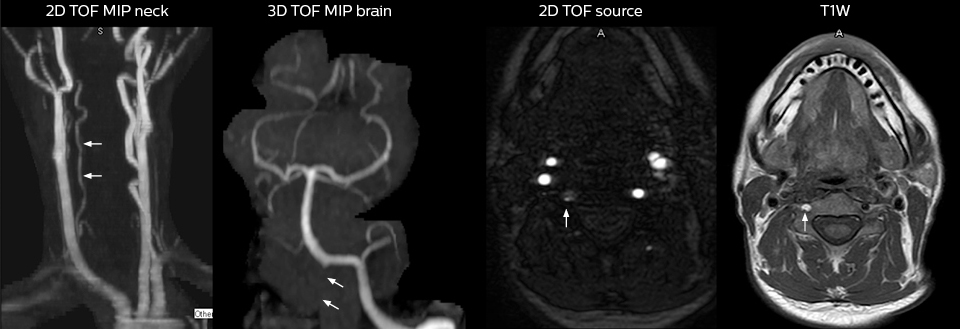

To minimize the time taken to perform scans, rapid MRI examination protocols (ExamCards) were developed, shortening the total scanning time to even less than 10 minutes in some exams. Techniques like mDIXON (modified DIXON) are used for robust capturing of fat-free MRI images in a hectic ED environment.

“We use mDIXON TSE extensively in our spine imaging in the emergency room,” says Dr. Karis. “It’s particularly nice in that it is very robust with regard to susceptibility type of problems that would come up with traditional spectral fat-saturated images; these problems are essentially eliminated with the mDIXON technique. In our ED environment it’s really nice to have the fat-free imaging that goes along with the mDIXON technique.

“For the thoracic and cervical spine routine non-contrast exam, for example, we perform one mDIXON T2 TSE sequence, which provides us with two outputs: the fat-and-water-together T2-weighted images, as well as the water-only sagittal T2-weighted images. And then we also perform an axial gradient echo exam.”